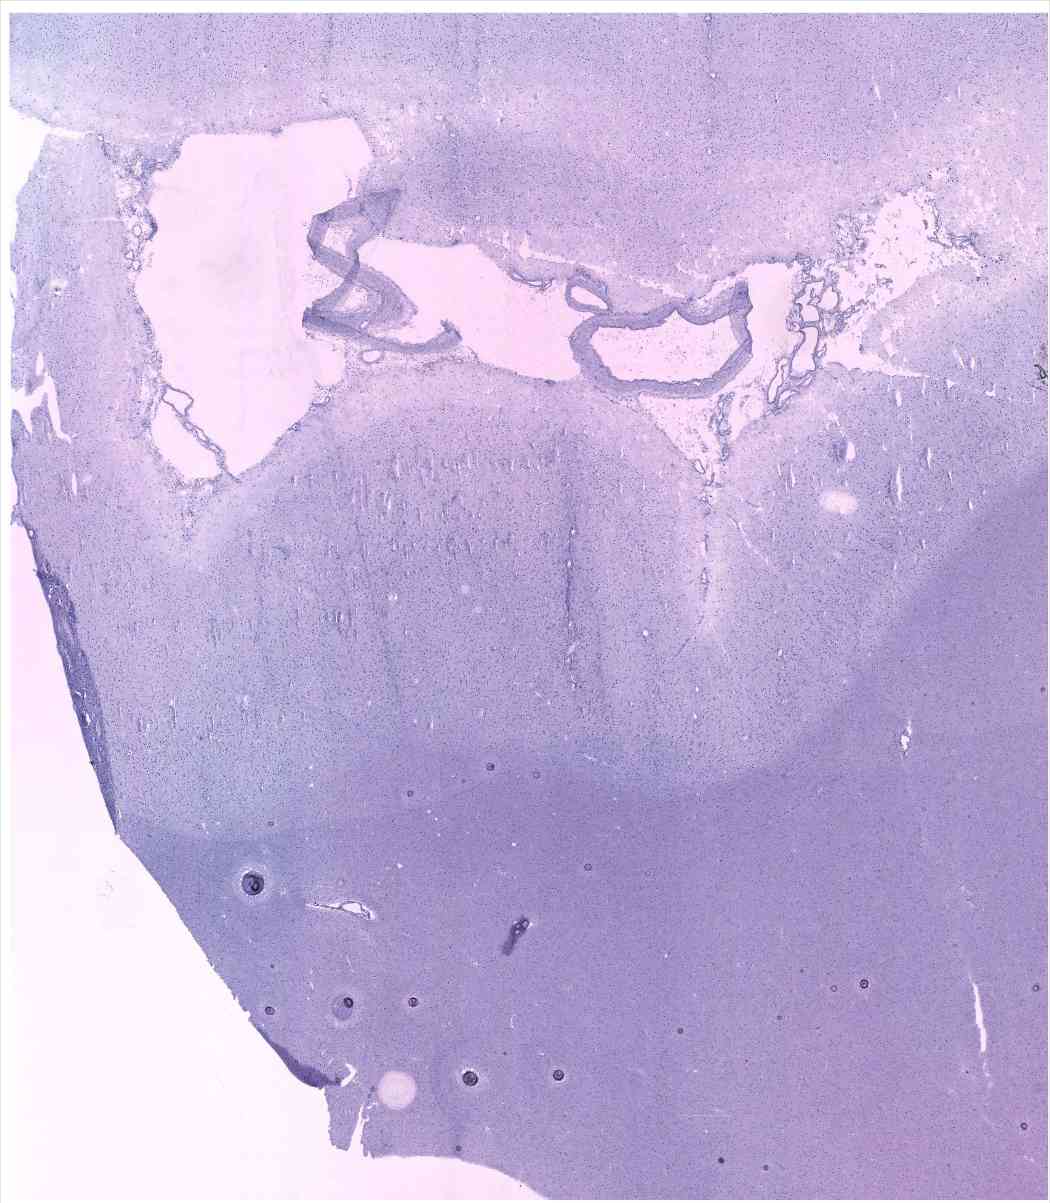

Chip 003 Well D1